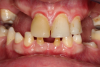

Fig 6. Photograph, 18-year-old brother.

Figure 6

Figure 5 through Figure 12 exemplify what currently may present in private dental practices with these types of patients. Four brothers aged 14 years to 27 years all suffered from obstructed airways; high incidence of caries of dentin, enamel, and cementum; moderate periodontal disease; collapsed vertical; undiagnosed OSA; and the potential for increase in comorbidities such as diabetes, cardiovascular disease, dementia, cancer, high blood pressure, and others. Symptomology was presented throughout the young lives of the brothers in this family. The parents were unaware that the dental agenesis and premature permanent tooth extraction could have led their sons into severe health issues as they matured.

Swift intervention took place with caries control, periodontal care, orthodontic evaluation for arch form development to aid in the development of facial bones and creating an improved upper airway with nasal patency. These interventions were followed up with definitive implant therapies and rapidly advancing restorative technology and materials. Thus, not only were these young men's smiles restored, they also were provided with the opportunity to regain their dignity when they become confident with their new smiles.